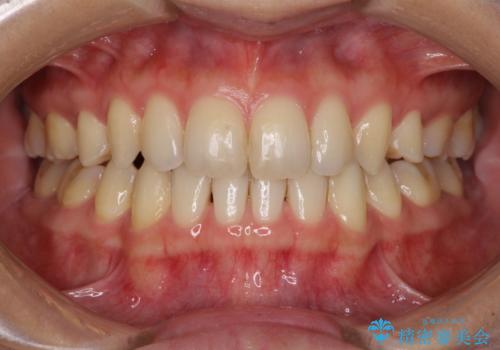

急速拡大とワイヤー抜歯矯正で唇を閉じやすく

- 口元の突出感を気にして来院された患者様です。

デコボコと口元の突出感が認められたため、上下左右の第1小臼歯4本を抜歯してのワイヤー矯正を行うこととしました。

上顎歯列幅を拡大したことで、デコボコを容易に解消することができるようになったため、抜歯により得られたスペースを口元の突出感改善に利用することができました。